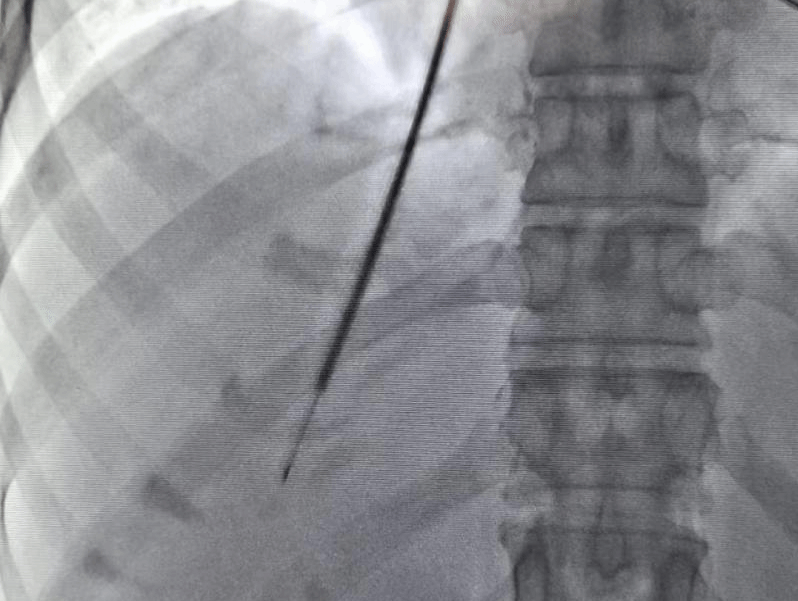

经颈静脉肝内活检术(X光下)

经颈静脉肝内活检术的出现为上述患者带来了福音,该技术能够将穿刺导引器从颈部静脉引导至肝内,安全有效的获取肝组织,解决了此类患者诊断难的问题。